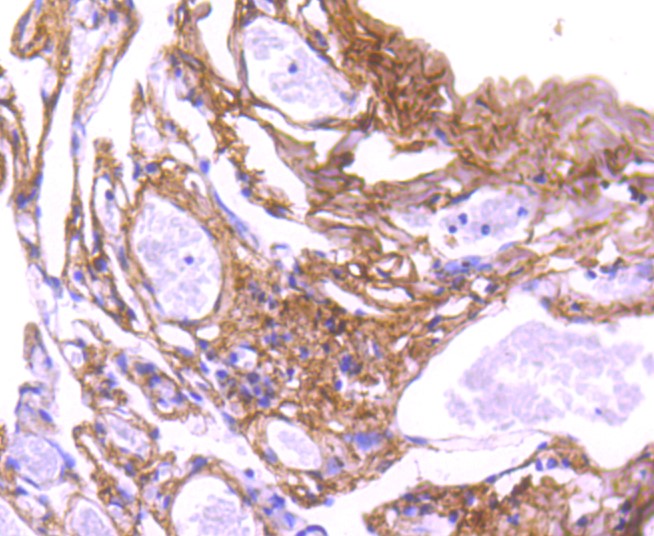

ApplicationsImmunoFluorescence, Western Blot, ImmunoCytoChemistry, ImmunoHistoChemistry, ImmunoHistoChemistry Paraffin

- ApplicationsImmunoFluorescence, Western Blot, ImmunoCytoChemistry, ImmunoHistoChemistry, ImmunoHistoChemistry Paraffin

- Applications SupplierWB(1:300-5000), IHC-P(1:200-400), IF(ICC)(1:50-200), IHC()